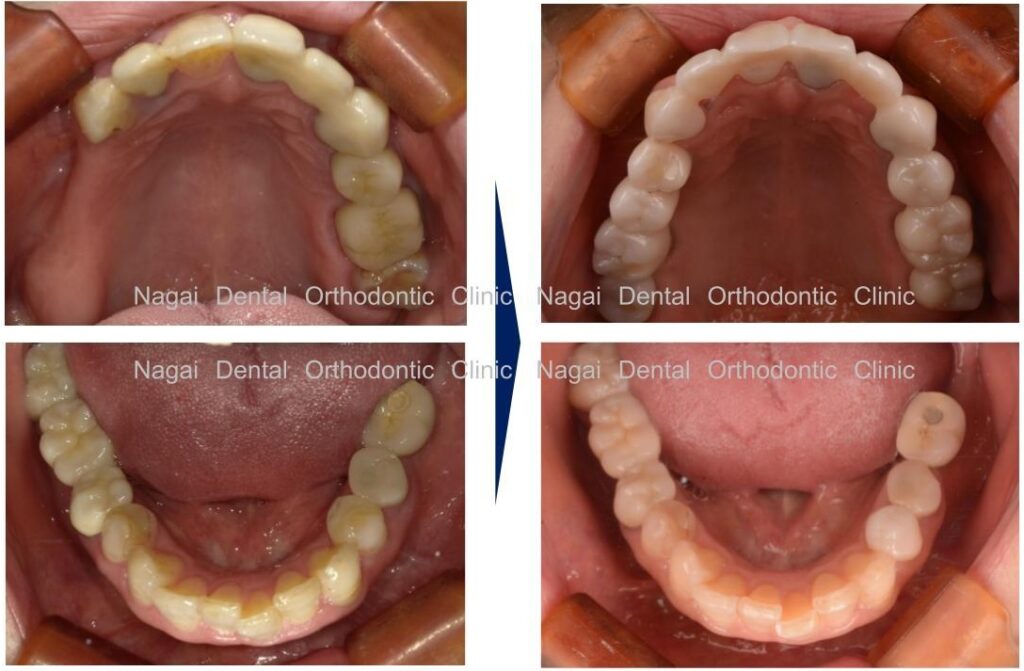

【口腔内の詳細変化】

▲部分欠損や咬合の乱れに伴う咀嚼能率低下の改善を図りました

▲部分欠損や咬合の乱れに伴う咀嚼能率低下の改善を図りました

▲インプラントによる固定式補綴物で、全体的な咬合の再構築を目指しました

| 治療内容 | 上下顎:オールオンフォー(チタンフレームジルコニアセラミック仕上げ) |

|---|---|

| 年齢/性別 | 50代/男性 |

| 背景 | 左側での咀嚼困難や、年々広がる歯間の隙間、および咀嚼時の不具合を主訴に来院されました。過去に部分入れ歯の適応を受けたものの、装着時の痛みから使用を中断されており、取り外し式の入れ歯以外の治療法を希望されていました。事前の咀嚼能率検査でも数値の低下が認められ、速やかな機能回復が求められる状態でした。 |

| 治療期間 | 約7か月(通院12回) |

| 費用 | 6,600,000円(税込)(片顎 3,300,000円×2) |

| リスク/副作用 | インプラント手術は、ご高齢の方や全身状態(持病など)によっては適応とならない場合があります。また、術後の口腔清掃を怠ると天然歯の歯周病に似たインプラント周囲炎が起こる可能性があるため、日々のセルフケアと定期的なメンテナンスが必要です。 |